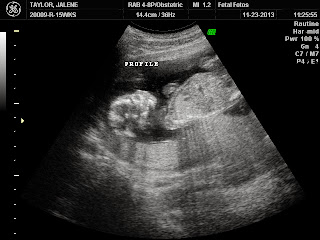

We are super impatient and couldn't wait until 20 weeks to find out what we were having, so we went to Fetal Fotos at 15 weeks. Again, me... nervous... worried that everything wouldn't look normal. And I had heard that same week of a girl due the day after me finding out she was pregnant with twins from her 3rd ultrasound! They only detected one fetus at ultrasound 1 and 2 and since I only had one ultrasound very early on, I started stressing they would find two babies in there! (I know, I stress about everything.)

She started the ultrasound and we were all smiles for the next 15 minutes. We finally got to see our baby who looked like a really baby! (And not a tiny blurry ball anymore.) She confirmed only one baby was in there... whew! I had thought the baby was a boy the entire pregnancy. Lincoln was sure it was a girl. The second she moved the wand to show his bum, I knew before she even said it. BOY! I could totally tell. We were (and are) so so happy! We got to see him do flips and move all around. He had his little ankles crossed and at one point, opened and closed his mouth a few times for us. He also got the hiccups twice, stretched out, and showed us a great shot of all five of his cute fingers on one hand.

I also think I may have felt him move for the first time the day before Thanksgiving! It's so hard to know what is gas bubbles and what is baby. But I was sitting on the couch and it felt like a tiny long potato did a flip or two in my lower abdomen. I've never felt anything like it, so I think it was him! I have felt little swishes and pokes about once or twice a day since then. He was sure active on our ultrasound so I wouldn't be surprised if it was him!